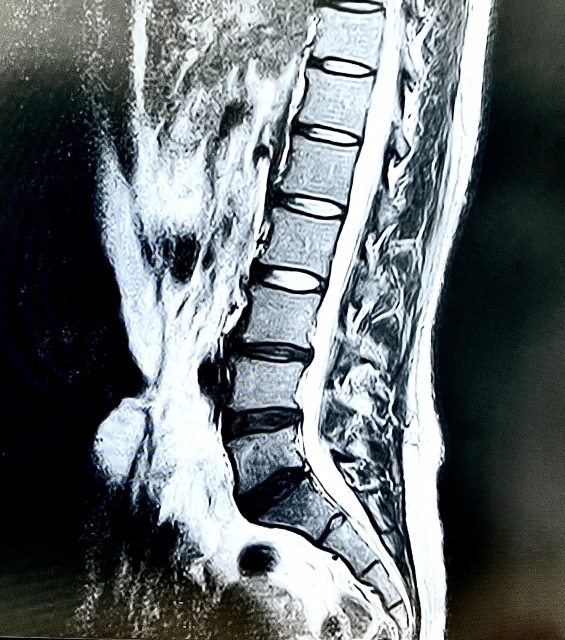

腰椎椎間板ヘルニアや坐骨神経痛など、神経を圧迫または刺激する疾患があると、足のしびれやジンジンとした痛み・だるさが現れることがあります。

神経は、電気信号のように身体中に「感覚」や「運動指令」を伝える役割を担っていますが、背骨のズレや筋肉のこわばりなどによって圧迫されると、正常な信号が送れなくなり、異常な感覚が生じます。

坐骨神経はお尻から太もも、ふくらはぎ、足の裏まで通っているため、神経の圧迫があるとこれらの部位すべてにジンジンと広がるような感覚が出ることもあります。

「片足だけにしびれが出る」「同じ場所に常に違和感がある」「腰にも違和感がある」場合は、神経性の症状を疑い、早めのケアが大切です。